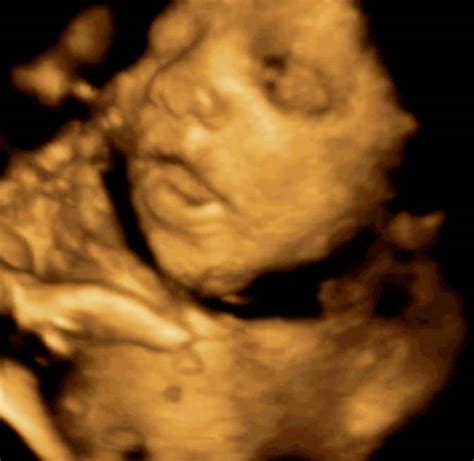

V 26. tednu nosečnosti otrok nadaljuje z rastjo in razvojem s hitrim tempom. Njegova velikost je primerljiva s plodom buče špagetarice ali pa koščka ohrovta, saj meri približno 35-36 cm od glave do pet in tehta med 750 in 850 grami. Glava otroka zdaj dosega velikost manjše pomaranče, s težo okoli 1000 g, medtem ko telo postaja vse bolj zaobljeno zaradi naraščajoče podkožne maščobe, ki bo služila kot rezerva ob rojstvu.

Razvija se tudi otrokov vid. Njegove oči so zdaj povezane z možganskimi predeli, ki so odgovorni za obdelavo vizualnih dražljajev. Kljub temu šarenica še nima dovolj pigmenta, da bi bila barva oči že razvidna, vendar pa se oblikujejo trepalnice, in kmalu bo otrok začel tudi mežikati.

Razlike med fazami, ko je otrok buden in ko spi oziroma počiva, postajajo čedalje izrazitejše. Ko je otrok aktiven, ga lahko čutite, kako se premika, ko pa spi, je v trebuhu vse tiho in mirno, vi pa nekaj ur ne zaznate popolnoma nobenega premikanja. Ta zaznava gibanja je ključnega pomena za spremljanje dobrobiti otroka.

Mreža živcev v ušesih je bolje razvita in bolj občutljiva kot prej. Plod lahko sliši vaš pogovor s partnerjem, prijatelji in sorodniki. Zato je že zdaj primeren čas, da mu začnete govoriti, saj dojenček že dojema vaš glas. Njegovi lasje in nohti so na dobri poti, pod dlesnijo pa so njegovi bodoči mlečni zobje skoraj pokriti s sklenino.